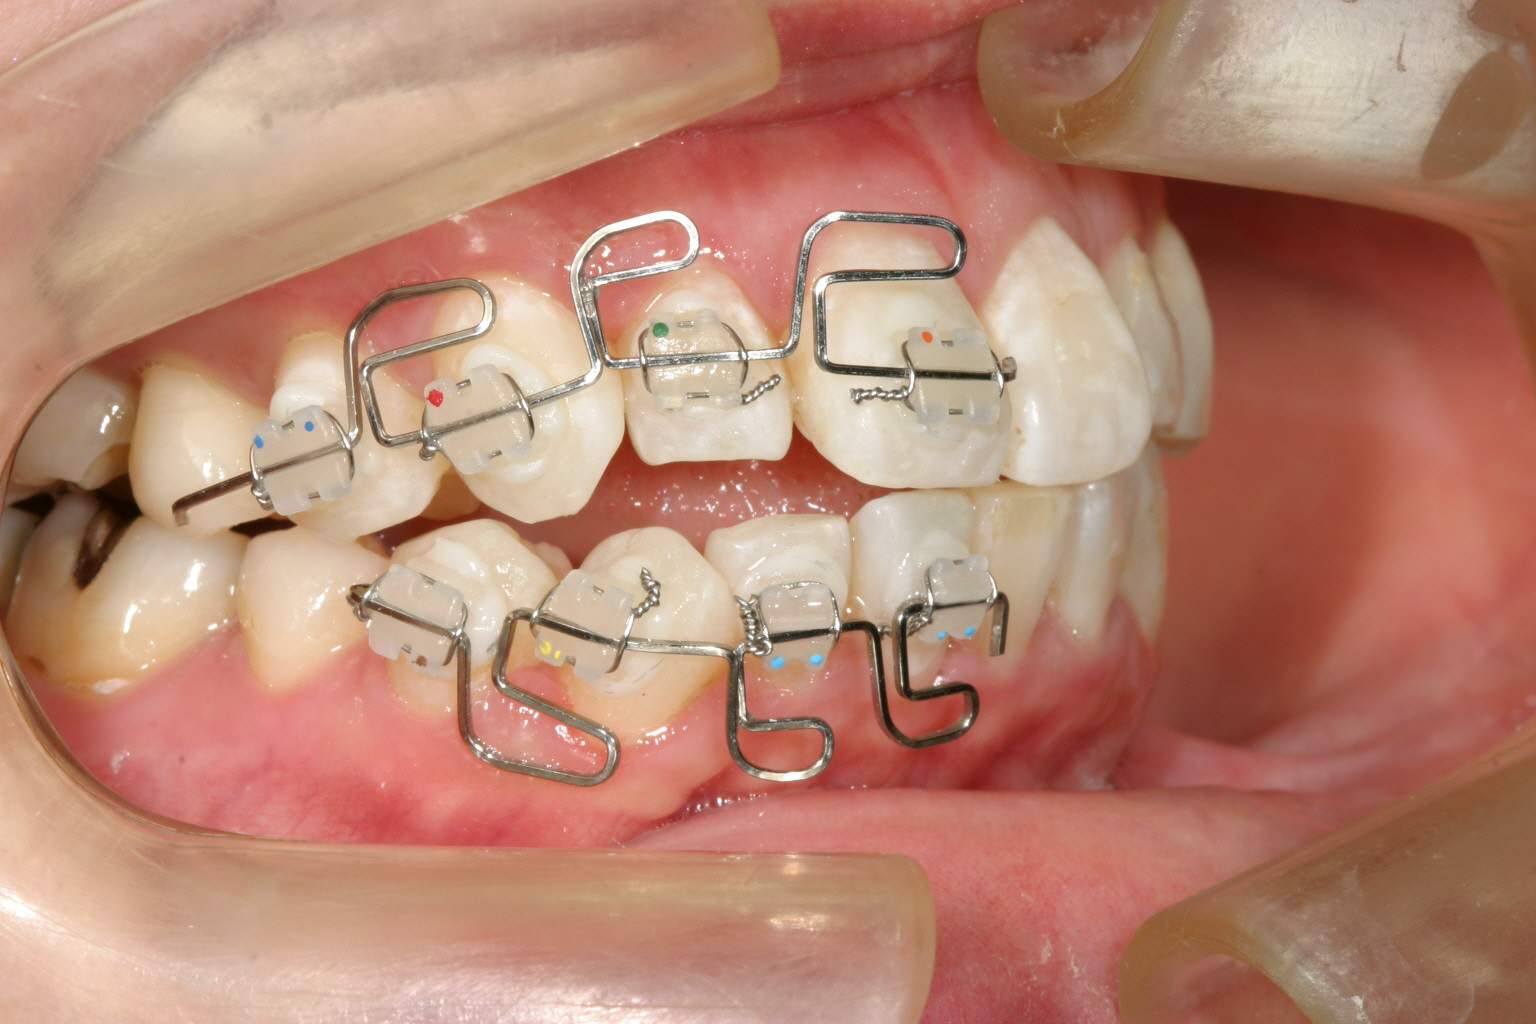

治療1年半後にマルチループにて咬合の修正を行っています。 特に下顎の犬歯の歪みを早く改善したいです。

マルチループワイヤー入れて2ヵ月でここまで修正完了です。 下顎犬歯の歪みも改善しました。